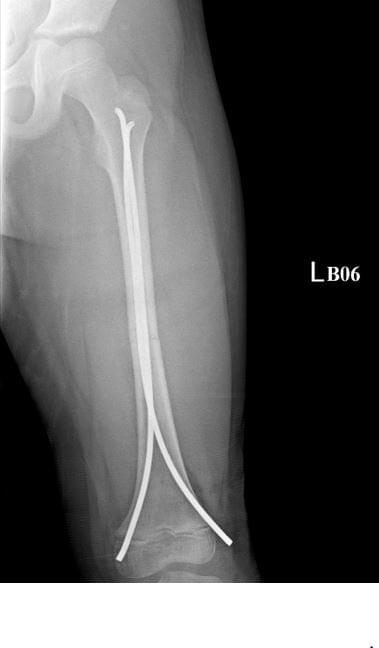

Femoral shaft fracture

- 如沒有明確受傷機轉,需懷疑家暴的可能,尤其是不會走路的小朋友(<1.5歲)

- 除嬰兒可以用Pavlik Harness治療外,其他全部都要進手術房處理。

- 如果是stable type且體重<45 kg,可以用TEN治療

- 如果是unstable type要用locking plate